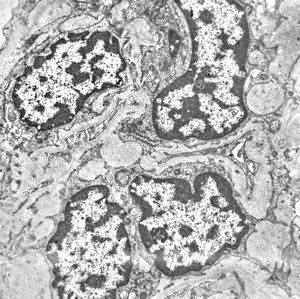

M,2y. | nephroblastoma (Wilms tumor)